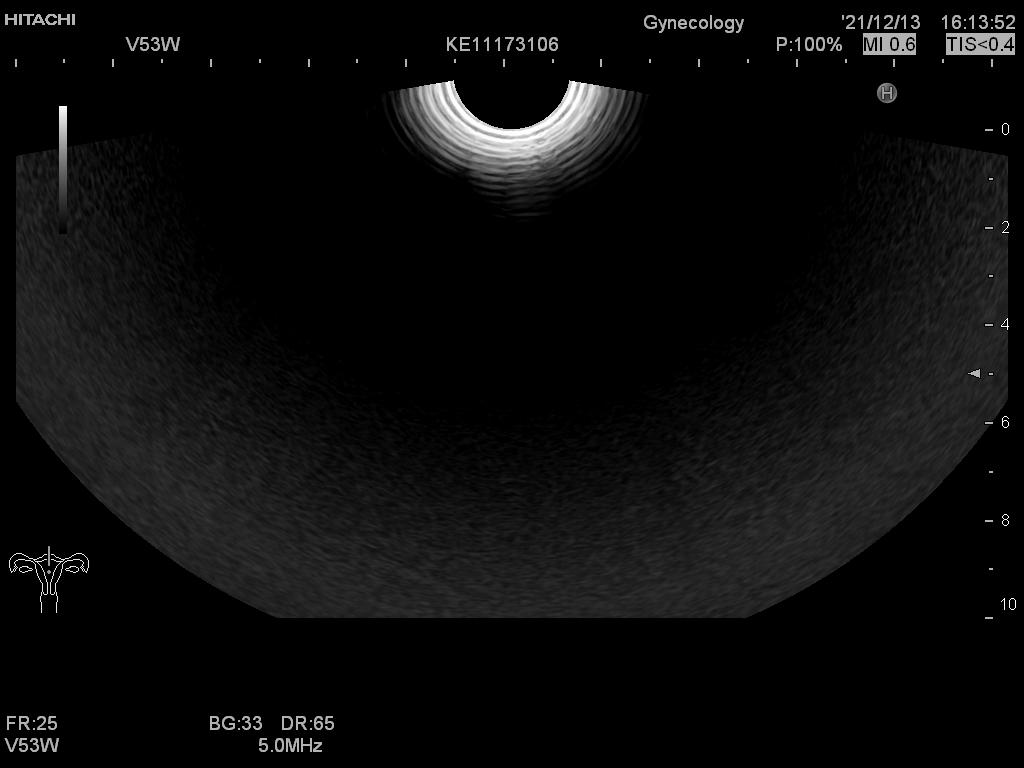

Hitachi EUP-V53W Endocavity Vaginal – HI VISION

Frequency Range: 8 – 4 MHz

Scan Angle Convex: 200° FOV

Hitachi EUP-V53W Endocavity Vaginal – HI VISION for Endovaginal

Compatible with Hitachi Hi Vision systems

| Radiology functions | Contrast Harmonic Imaging (CHI), Elastography (RTE), RT Sonography (RVS) |